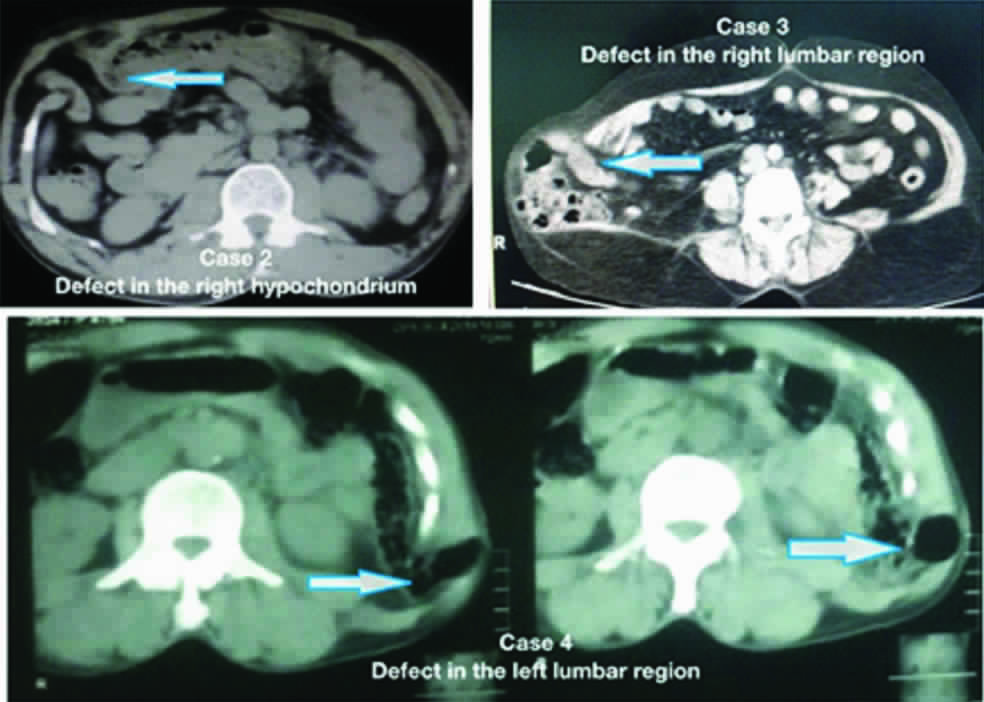

A 27-year-old male patient had a fall from a two-wheeler with impact in the right hypochondrium and was brought to emergency department. Examination revealed generalised tenderness and a palpable defect. Contrast Enhanced Computerised Tomogram (CECT) abdomen was done revealing herniation of bowel through a muscular defect [Table/Fig-2]. He was taken up for emergency laparotomy, done through an incision over the defect. Intraoperatively, mesenteric tear with small bowel contusion was noted. Primary tissue repair was completed [Table/Fig-3]. No complications were noted in the ten days postoperative period.

CT Abdomen images of the patients showing muscular defect with bowel herniation corresponding to the site of injury.

A 34-year-old male patient had a road traffic accident with blunt injury on his right lumbar region. On examination, there was a reducible swelling and a palpable defect at the same site [Table/Fig-1]. CECT abdomen was done, showing a lumbar hernia [Table/Fig-2]. He was taken up for emergency surgery. Incision was placed over the swelling, and abdomen opened. No bowel or solid organ injury was noted. Mesh repair was done [Table/Fig-3]. Postoperative recovery was complete and uneventful during the follow up period of six months.

A 60-year-old male, was admitted with history of fall from two wheeler and blunt injury to left lumbar region [Table/Fig-1]. No other external injuries were noticed. Examination revealed a palpable reducible swelling. CECT abdomen was done which showed left lumbar hernia [Table/Fig-2]. Emergency surgery was performed. There was no intra abdominal injury. Primary tissue repair was done [Table/Fig-3]. He had uneventful postoperative recovery and was followed up for a period of six months.